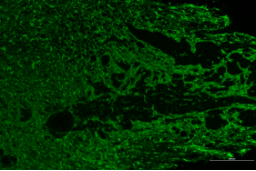

正常對(duì)照組 模型組

脊髓損傷模型GFAP表達(dá)差異對(duì)比

免疫熒光技術(shù)是將免疫學(xué)方法(抗原抗體特異結(jié)合)與熒光標(biāo)記技術(shù)結(jié)合起來研究特異蛋白抗原在細(xì)胞內(nèi)分布的方法。由于熒光素所發(fā)的熒光可在熒光顯微鏡下檢出,從而可對(duì)抗原進(jìn)行細(xì)胞定位,并且可以通過熒光強(qiáng)度對(duì)檢測蛋白的表達(dá)量進(jìn)行半定量分析。